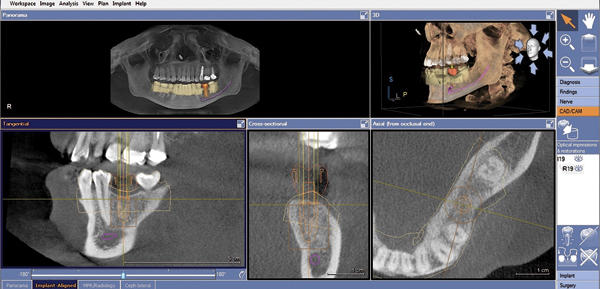

Once the desired restorative outcome is in a digital format, the patient’s CBCT scan is opened in the implant-planning software. If the edentulous space is in the posterior mandible, the inferior alveolar nerve bundle (IANB) is traced so that it is highlighted and avoided by the planned implant (Figure 2). Now, the patient’s digital restoration can be imported. Once imported, most software requires the user to identify corresponding landmarks on the digitized model and on the CBCT to merge the two data sets. It is best to avoid using teeth with crowns or large restorations as landmarks, because they cause distortions in CBCT scans and may result in inaccuracies in data set merges. Once complete, merge accuracy is verified by the user and is either confirmed or reset.

Figure 2. Cone-beam computed tomography (CBCT) with traced and highlighted inferior alveolar nerve bundle (IANB).

Figure 2

Figure 3. CBCT with final implant plan. Note the digital restoration, TiBase abutment, and highlighted IANB.

Figure 3